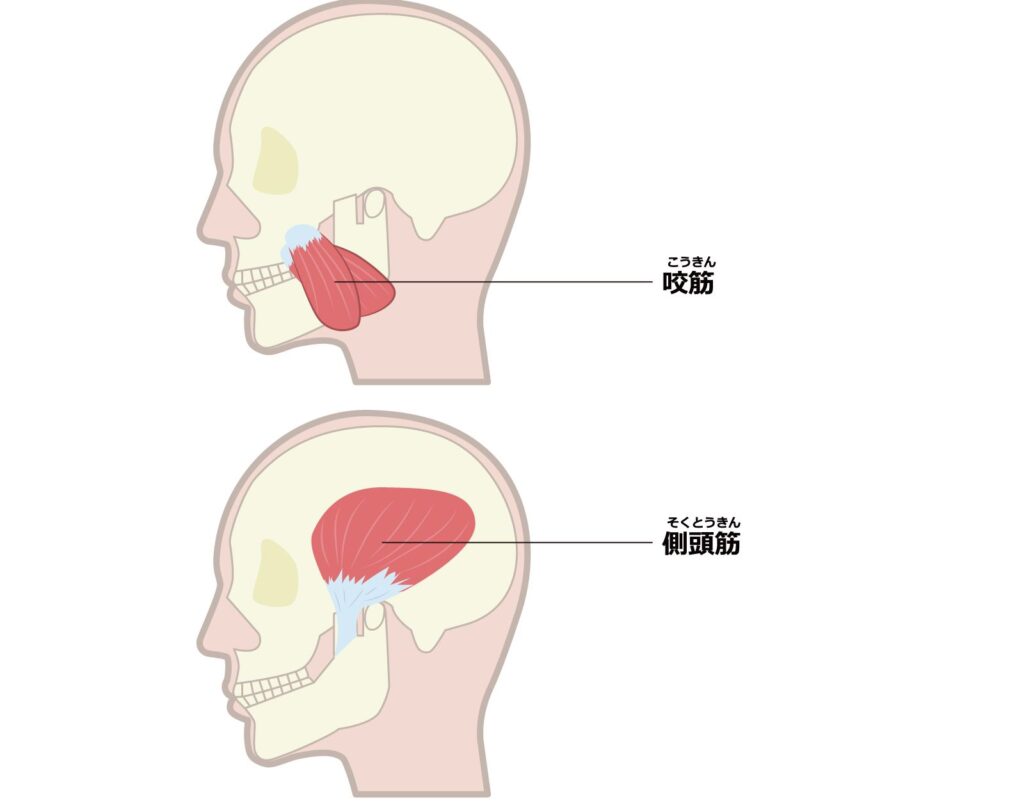

- 咬筋(噛む筋肉)の強い過緊張

食いしばりが首痛を引き起こすメカニズム

食いしばり・歯ぎしりがあると、

- 胸鎖乳突筋

- 斜角筋

- 広頚筋

といった、耳〜鎖骨の下(第一肋骨)にかけて走る筋肉が強く緊張します。

これらの筋肉が縮こまることで、

- 顔が下を向いた姿勢

- 首が前に倒れた状態(ストレートネック傾向)

になりやすくなります。

その姿勢では奥歯が噛み合いやすくなり、 さらに首の前の筋肉・咬筋・側頭筋が緊張 → 食いしばりが助長される という悪循環に陥ります。

特に側頭筋(こめかみにある筋肉)は、

- こめかみを走る神経(三叉神経の枝)

- 血管(浅側頭動脈)

を圧迫するため、側頭部(こめかみ)の頭痛を引き起こすこともあります。